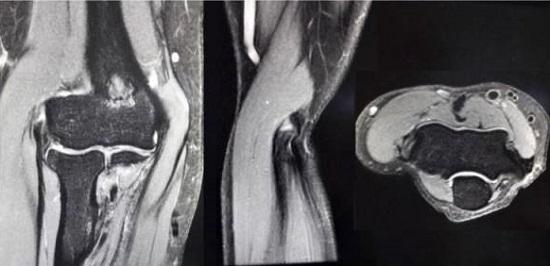

1、查体。用手指按压肱骨外上髁(上臂末端外侧区域),会有比较明确的、敏锐的疼痛;在肘伸直、握拳、屈腕状态下前臂旋前,会在该区域出现显著疼痛;前臂旋前的情况下负重旋后,也会出现疼痛。中期和早期的患者,不会在肱骨外上髁处出现肿胀等异常表现,长期的患者可能会出现伸腕肌的萎缩。 2、影像学检查。X光一般没有异常(比较严重者可能会有钙化点);超声波检查可能会发现肌腱纤维化、钙化等表现;MRI(核磁共振)检查可以较好地观察到软组织和骨骼病变,但对初期的病变仍难以探查。 3、鉴别诊断。如有外伤史,或者是短期内出现的急性疼痛,亦或同时存在神经病变的症状(感觉缺失、烧灼痛等),应通过影像学检查、查体、病史询问等方式与骨折、韧带损伤、肌腱断裂、神经病变等疾病进行鉴别诊断。